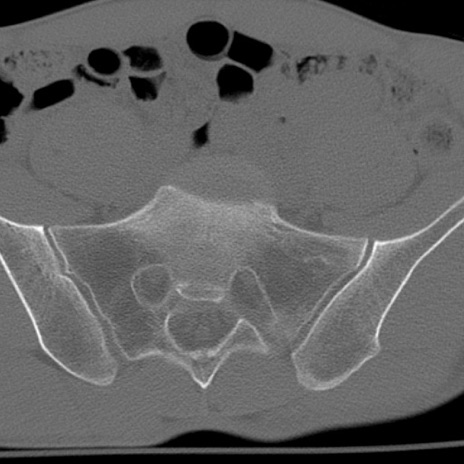

症例3 腰椎CT(横断像)

腰椎CT